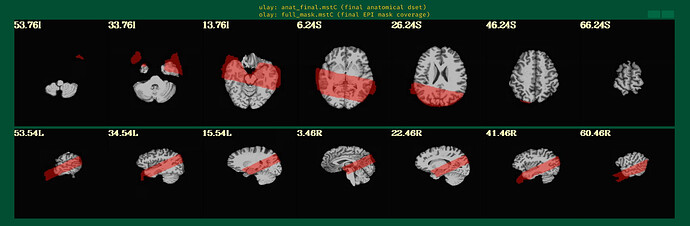

Is there a possibility to include a full brain volume (which I acquired on many more slices and totally aligned with the time series focused on hippocampus) in the afni_proc command or have I done any mistake in my command which follows?